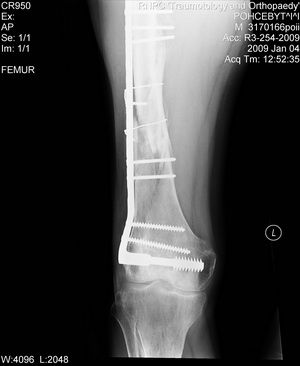

Больной 42 лет получил перелом проксимального отдела бедра. Ранее (1 год назад) оперирован на том же бедре по поводу оскольчатого диафизарного перелома. Четкой консолидации диафизарного перелома на рентгенограммах нет. Сопутствующие заболевания - tbs и гепатит С. При обсуждении хотелось бы услышать варианты лечения 1) "в идеале" и 2) с учетом социального статуса. Спасибо, А.Ситник

На снимке есть только дистальный отдел бедра, похоже, еще (или уже?) несросшийся на

фоне DCS. Что за перелом проксимального бедра, пока информации нет. Шлите снимки. И узнать бы, что доступно на месте для этого пациента.

Теперь ситуация более ясная. Оптимальным тут, очевидно, было бы малоинвазивное удаление пластины и закрытый интрамедуллярный остеосинтез длинной гаммой или другим проксимальным гвоздем. Это не только обеспечило бы надежную фиксацию всех проблемных отделов бедра, но и позволило бы немедленную полную нагрузку.

Другие варианты менее привлекательны, хотя в итоге могли бы привести к успеху. Но ценой большей травматичности, длительности лечения, неудобств, трудоемкости и с бОльшими рисками неприятностей. Вариантов очень много - скелетное вытяжение, тазобедренная повязка, остеосинтез DHS или другой пластиной с угловой стабильностью, остеосинтез таким или другим аппаратом...